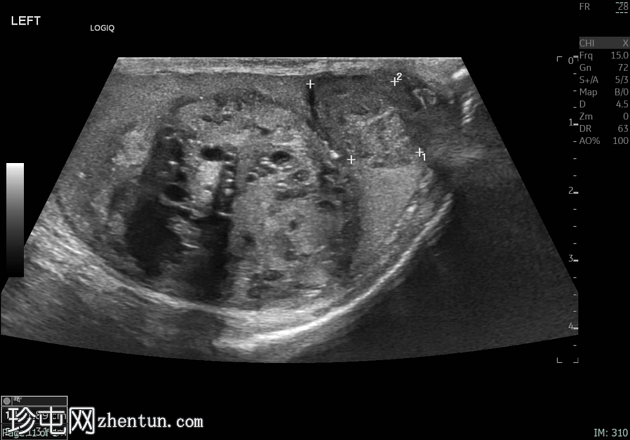

左侧睾丸肿大,体积约56 mL,可见弥漫性微结石,以及三个内部等回声病灶,伴囊性变、微钙化和明显血流信号,最大病灶大小约4.8 x 3.2 cm。

未见腹主动脉旁或髂淋巴结肿大。